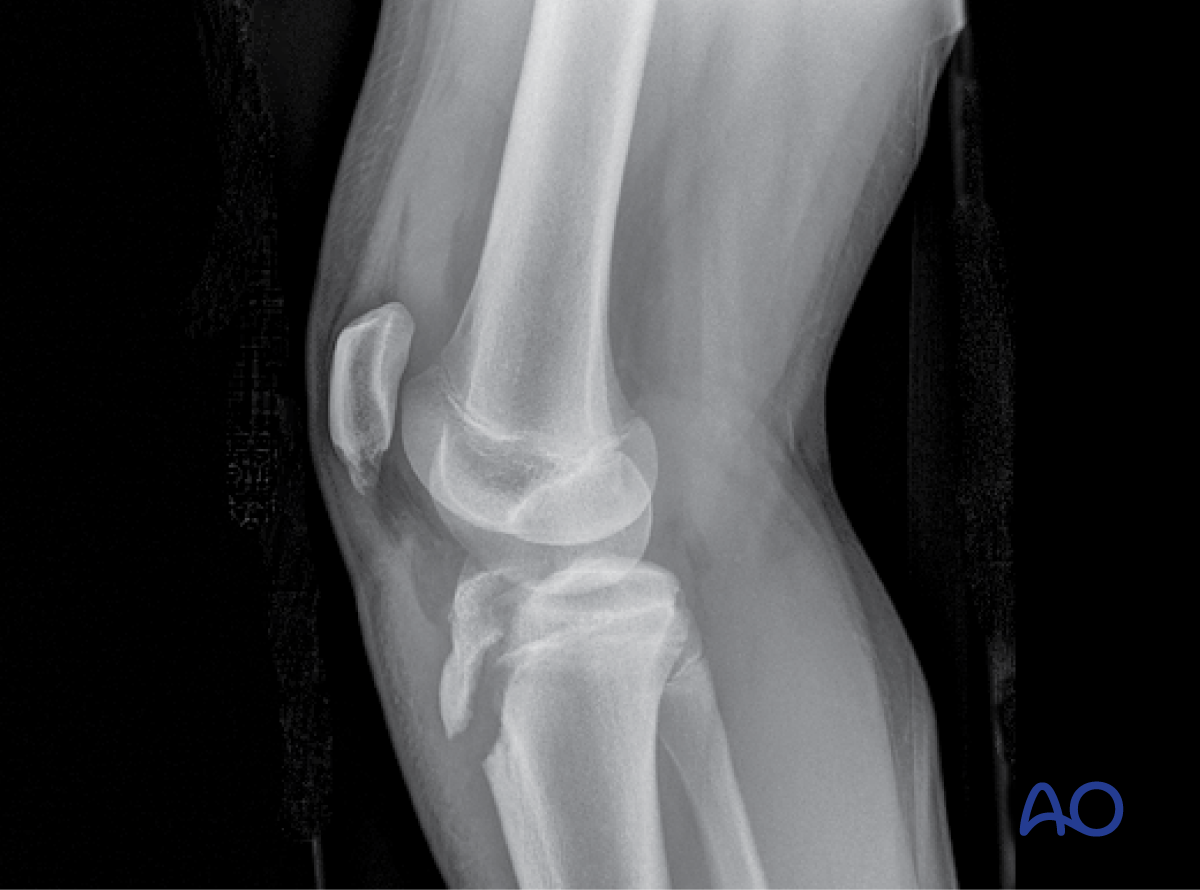

This module includes a detailed consideration of all patterns of physeal injury using a spectrum of techniques. A description of bridge plating has also been introduced, which is relevant to the older child in addition to specialist techniques, which combine conventional osteosynthesis with arthroscopy to manage intraarticular fractures.

- Salter-Harris type-I–IV fractures

This includes detailed procedures on K-wire and screw fixation, external fixation, plate fixation, in addition to nonoperative management with casting and splinting.